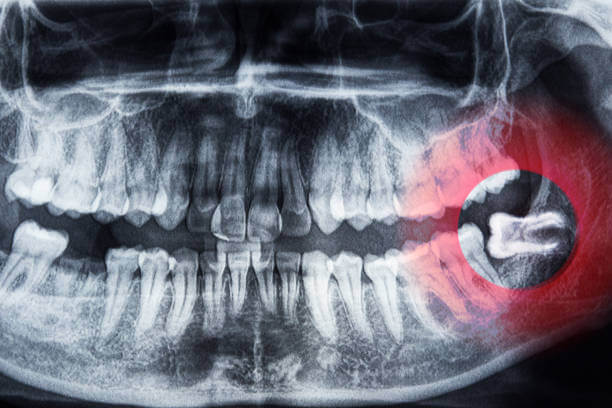

사랑니는 대부분 치아 뒤쪽에 위치해 제대로 자라지 못하고 염증, 충치, 잇몸질환 등을 유발합니다. 이럴 경우 건강보험 적용이 가능하며, 일부는 실손의료보험(실비보험) 청구도 가능합니다.

- 건강보험 적용: 통증, 염증, 감염, 기능적 문제 있을 시 적용

- 실비보험 적용: 수술적 발치(매복 사랑니 등) + 진단서 필요

- 매복 사랑니 발치로 잇몸 절개, 골삭제, 봉합이 필요한 수술코드가 발생한 경우

- 통증·염증 등의 질병 사유로 인해 발치가 의학적으로 필요한 경우